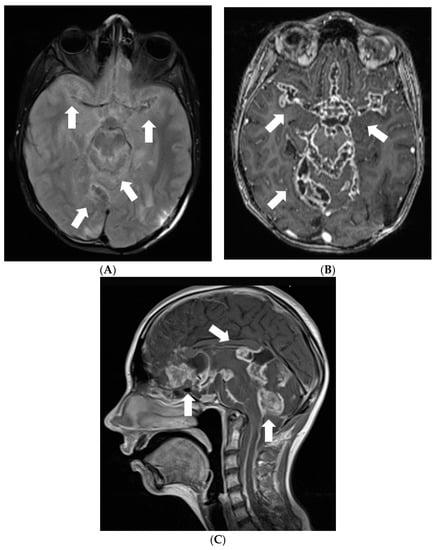

After 4 months when symptoms of raised intracranial pressure recurred, additional findings were detected on follow-up MRI. Most of the subarachnoid cisterns, Sylvian fissures, sulci of superior parts of the cerebellum, and the lower part of the fourth ventricle were filled with diffuse non-contrast-enhancing multiple small cyst-like lesions (Figure 3). These lesions were more evident on T2W/FLAIR and T2W/SPC images; T2W/FLAIR revealed iso/slightly hypointense lesions resembling cysts in the previously mentioned areas. The lesions did not show diffusion restriction or any significant compression of adjacent structures. Additionally, magnetic resonance spectroscopy of the lesion demonstrated lactate peak. Due to the uncertain origin of the findings, a biopsy of the newly detected tissue in the perimesencephalic cistern was performed. Histological appearance and immunohistochemical phenotype of the sample were the same as in the previous examination, consistent with subarachnoid spread.

Figure 3.

Follow-up MRI of the brain 1 year after the onset of the symptoms (April 2012): (A) Axial T2W/FLAIR/FS and (B) T2W/SPC images disclose masses composed of multiple small cysts in the subarachnoid cisterns, Sylvian fissures, and cerebellar sulci. There is no contrast enhancement (C) in the referred areas.